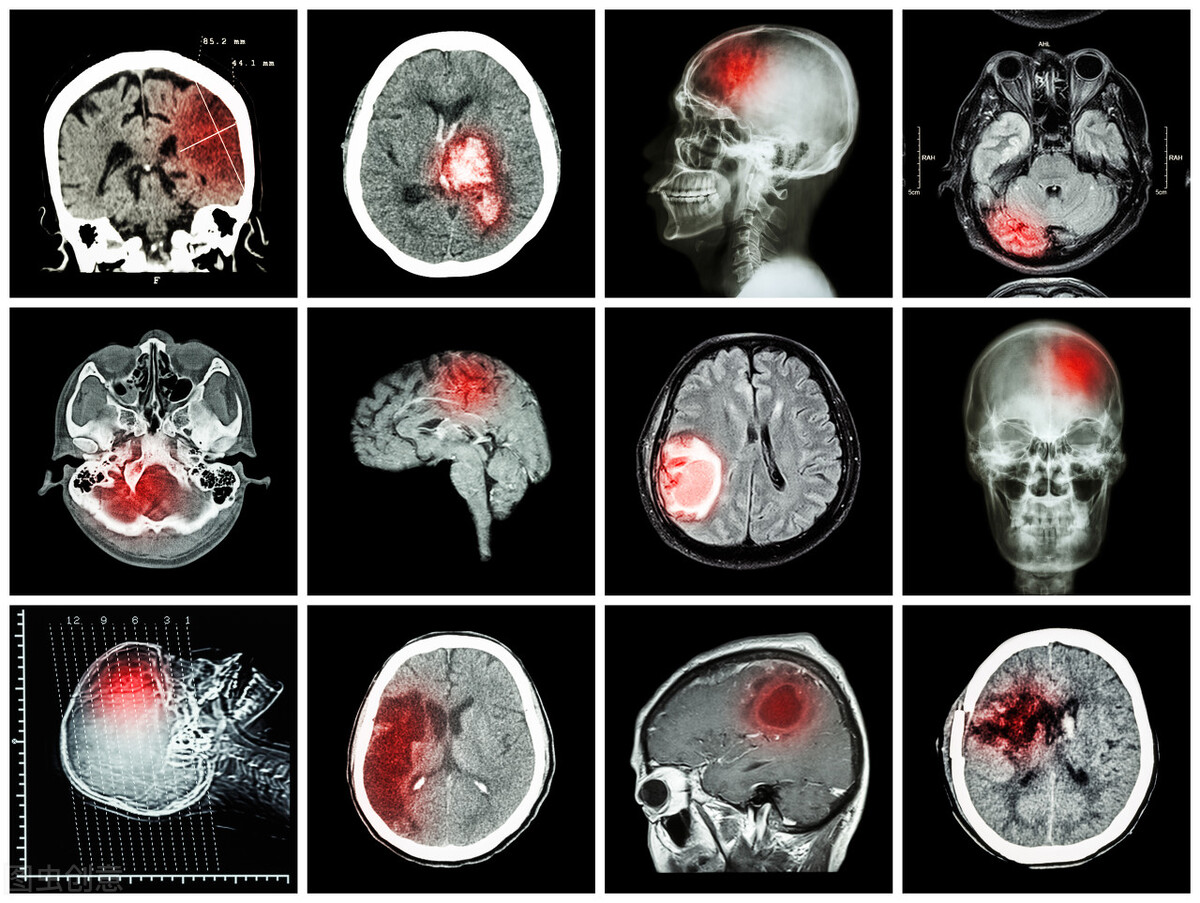

近年随着人民生活水平的提高,人口老龄化日益严重,卒中发病率亦在逐年上升世卫组织调查结果显示:中国脑卒中发病率排名世界第一(每年约200万人),比美国差不多高出一倍。

卒中后肌肉痉挛是脑卒中后常见的运动神经元病损后,由于脊髓和脑干反射亢进而出现的肌张力异常增高的综合征。急性脑卒中,开始时会出现软瘫,即肢体无力比较严重、肌张力低、运动困难等。

脑卒中后痉挛是指脑卒中后运动神经元病损后,由于脊髓和*干高**反射亢进而出现的肌张力异常增高的综合征。表现为间歇性或连续性的肌肉不随意收缩。脑卒中后痉挛的常见症状有:肌肉张力增加、肌肉僵硬或紧张、肌肉反复快速收缩、关节僵硬。